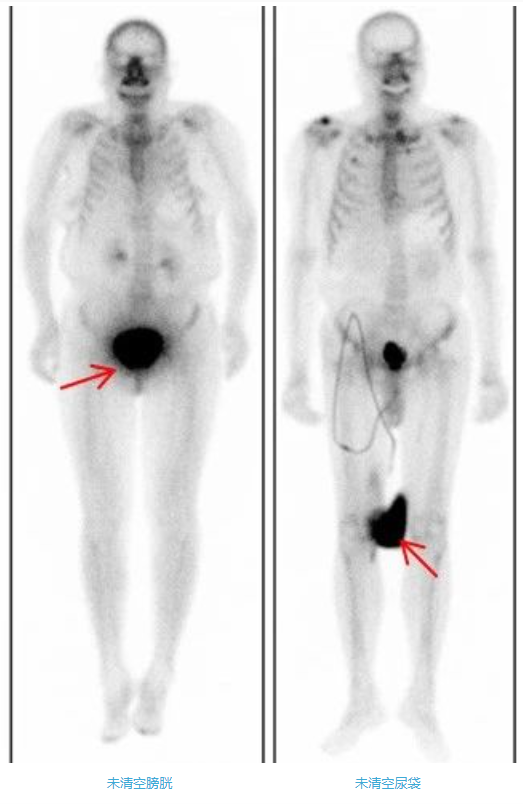

4、多喝水,清空膀胱

注射骨顯像劑后2-5小時(shí),50%-60%顯像劑沉積在骨骼中,剩余的顯像劑或潴留在肌肉或通過(guò)尿液排出體外。為了提高骨骼圖像質(zhì)量,注射骨顯像劑后,需要注射后多飲水(一般500ml-1000ml,受檢者如無(wú)明顯不適可增大飲水量)、多排尿。大量小便潴留在膀胱內(nèi),會(huì)影響骨盆區(qū)骨骼的判讀,所以掃描前要清空膀胱。排尿時(shí)須避免尿液污染皮膚和衣物。一旦污染了衣物,形成放射性偽影,會(huì)影響圖像質(zhì)量和結(jié)果判讀,因此需更換衣物或清洗污染部位后重新進(jìn)行掃描。如果患者有尿袋,檢查前需要清空尿袋;同樣注意避免污染皮膚和衣物。